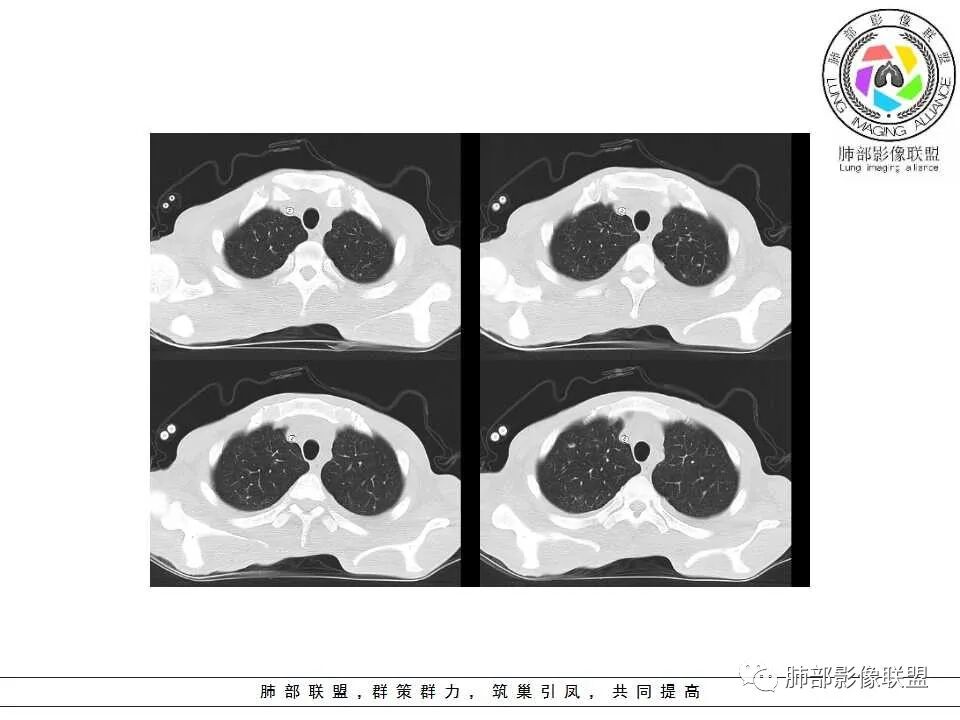

3.心腔内密度减低(提示贫血或其他恶液质可能)。